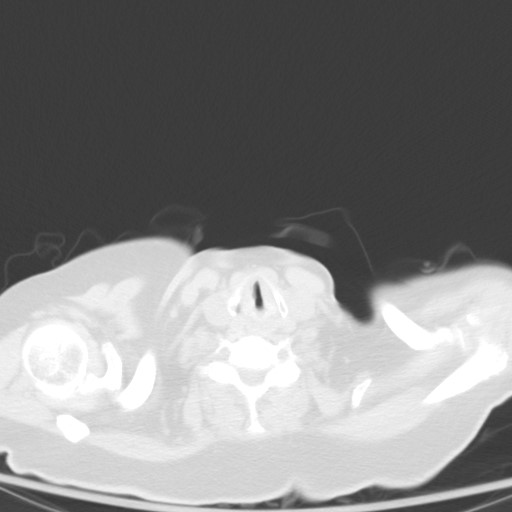

We then reviewed the CT and determined it was bronchiectasis:

• Bronchioectasis is defined as “Irreversible dilation and destruction of larger bronchi caused by chronic infection and inflammation”

• Radiographic Findings

• The internal diameter of the bronchus is larger than that of its accompanying vessel

• the bronchus fails to taper in the periphery of the chest